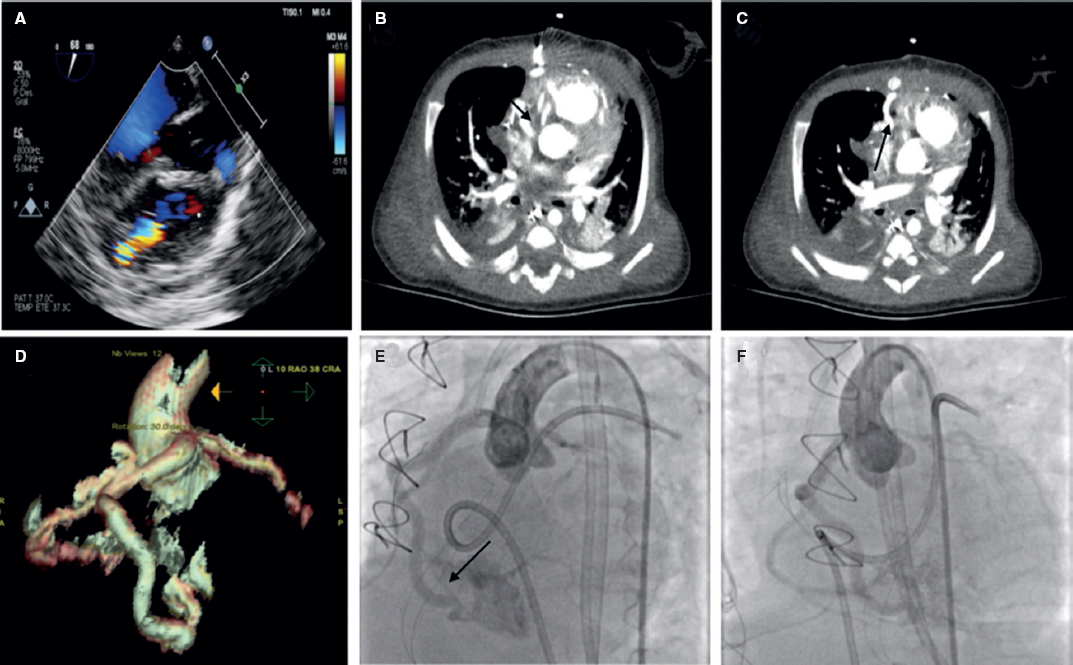

Lactante de 2 meses recientemente intervenido de cierre de comunicación interventricular perimembranosa con clínica congestiva en el posoperatorio y sospecha ecocardiográfica de posible fístula de coronaria derecha a ventrículo derecho, confirmada con la realización de una tomografía computarizada cardiaca y un cateterismo con coronariografía no selectiva. Se obtuvo el consentimiento informado de los padres para la difusión del caso. Se observa una gran fístula coronaria desde la rama marginal de la coronaria derecha desembocando en la cavidad del ventrículo derecho con gran dilatación del segmento proximal de la coronaria derecha (figura 1) favorable para cierre percutáneo. Con un catéter transportador de 4 Fr sondando la coronaria derecha se avanza una guía coronaria hasta el ventrículo derecho y, asistido por balón de angioplastia, se avanza el catéter transportador hasta la zona proximal de la fístula, donde se libera un dispositivo Amplatzer Vascular Plug (AVP4) (Abbott, USA) 4 × 6, con oclusión completa del defecto sin interferencia con la coronaria derecha distal (figura 2).

Figura 1.